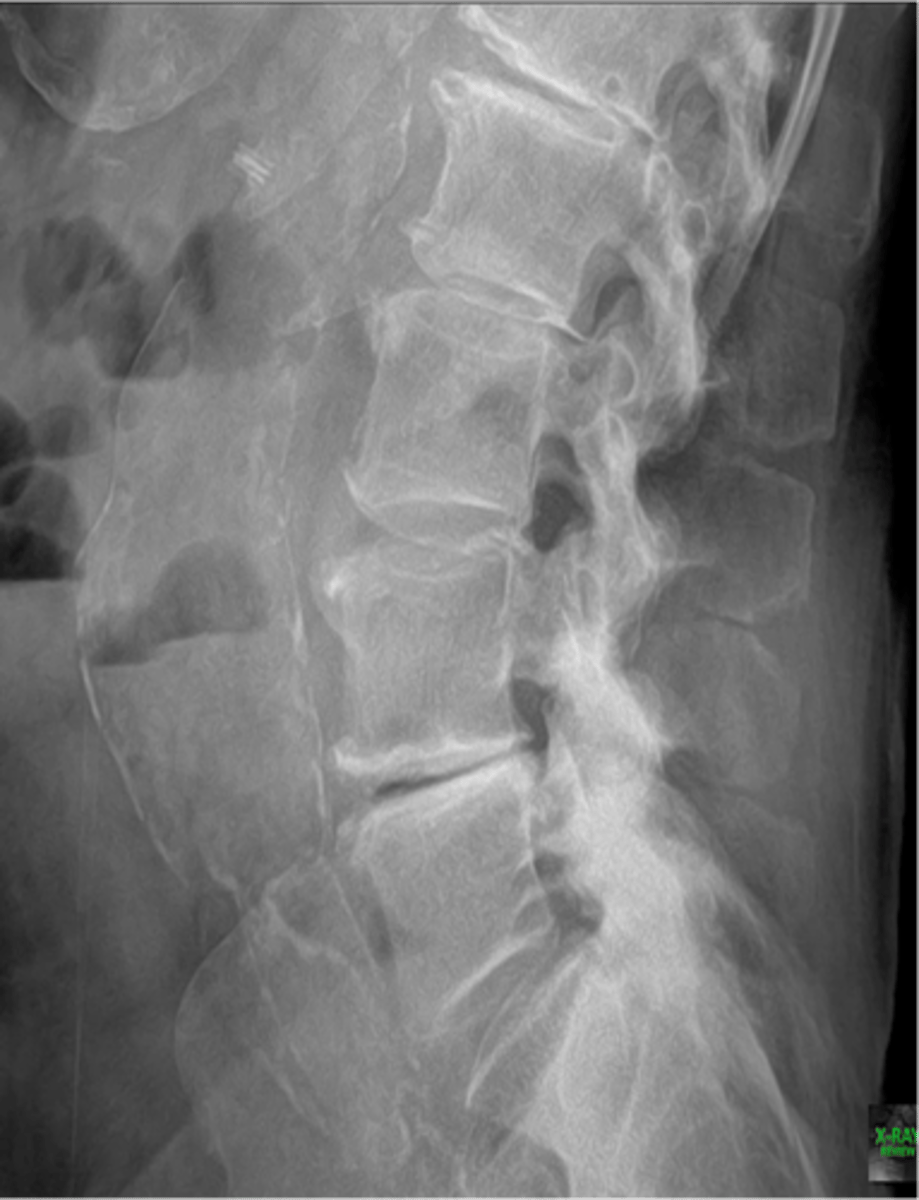

Abdominal aortic aneurysm calcification

Abdominal aortic aneurysm calcification (pic 2)